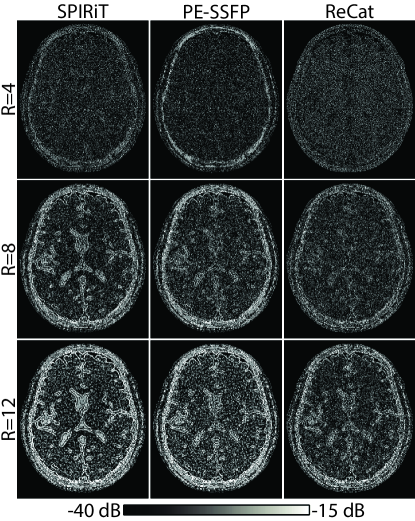

ReCat was first demonstrated on bSSFP acquisitions of a numerical brain phantom with D=8. ZF, SPIRiT, PE-SSFP and ReCat reconstructions and error maps are shown in Fig. 3. Error maps for varying acceleration factors R= are shown in Fig. 4. SPIRiT that independently processes separate acquisitions and PE-SSFP that independently processes separate coils suffer from broad errors at high-spatial frequencies. In comparison, ReCat achieves visibly reduced reconstruction error and enhanced tissue depiction, particularly for R4.

Quantitative assessments regarding ReCat and alternative reconstructions are listed in Table 1 for N=2-8 and R=4-16. ReCat yields higher PSNR values compared to SPIRiT and PE-SSFP at all N and R, except for two cases R=4, N=8 and R=4, N=4 where the techniques perform similarly. On average, ReCat improves PSNR by 2.01.0 dB over SPIRiT, and by 2.00.5 dB over PE-SSFP (meanstd across subjects; average for N=2-8, R=8-16).